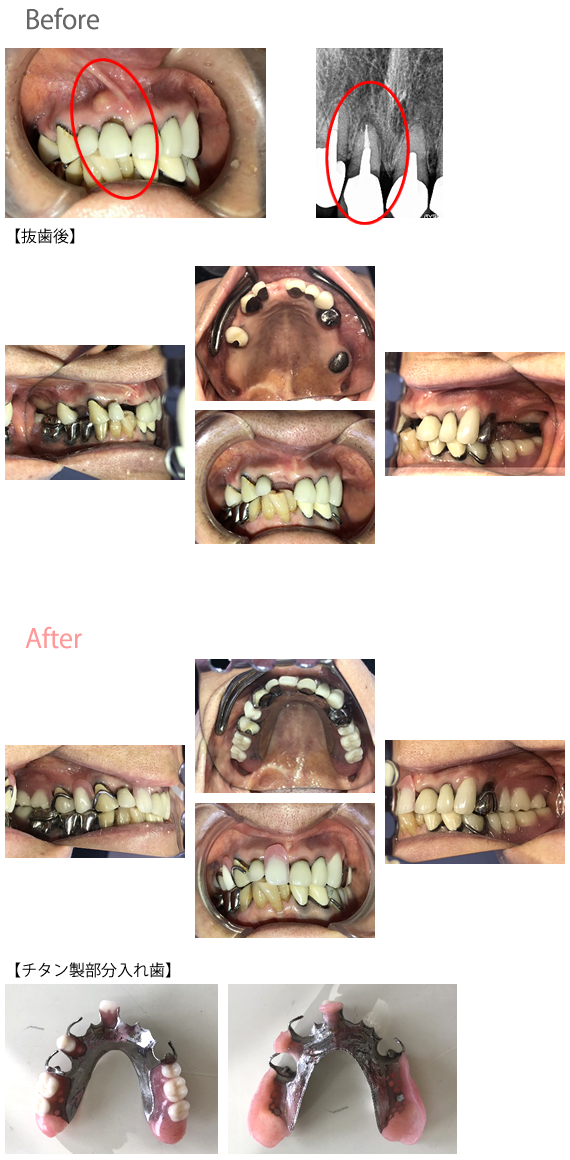

男性 Kさん 60代(チタン製義歯)

主訴

歯がないところに入れ歯をいれたい。

治療内容

チタン製の部分入れ歯を入れました。

所感

以前、他の医院で保険の部分入れ歯を入れたことがあるそうですが、痛くて使えなかったそうです。今回は、チタン製の部分入れ歯を希望されました。チタン製の部分入れ歯は、保険の部分入れ歯に比べ、構造が頑丈にできているため、噛んだ時に入れ歯のゆがみが少ないため、歯茎にあたっていたいという事が少ないです。部分入れ歯を選択する場合は、チタン製の部分入れ歯を選択されるのが最良だと思います。

チタン製部分入れ歯:¥297,000(税込)